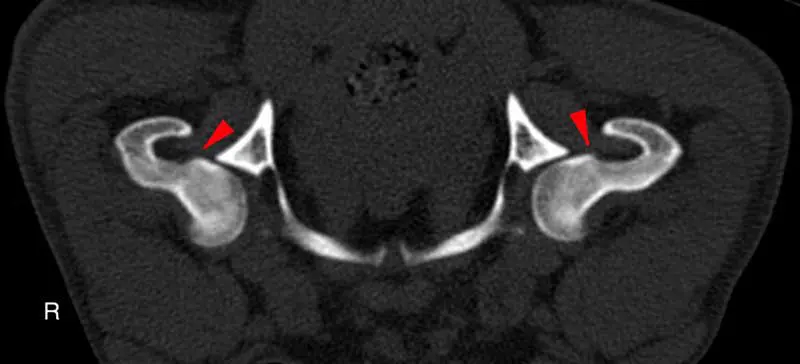

Risk assessment of all patients in for routine appointments will help to identify those that are most likely to have or develop degenerative joint disease. Risks include breeds with a genetic predisposition for OA, working and sporting dogs, dogs with a history of joint trauma or joint surgery, those that have high adiposity, or those entering senior life stage. Patients with risk factors but no symptoms may be regarded as having “pre-clinical” OA and, therefore, it is appropriate to closely monitor for development of discomfort or functional changes that could signal the onset of clinical OA, to ensure prompt intervention if needed. Diagnostics at an early stage of OA has been shown to be challenging. Radiography detects changes later than imaging such as CT, while MRI can detect even earlier changes and is the first imaging modality to be able to directly image cartilage (Figures 2 and 3; Jones et al, 2022).